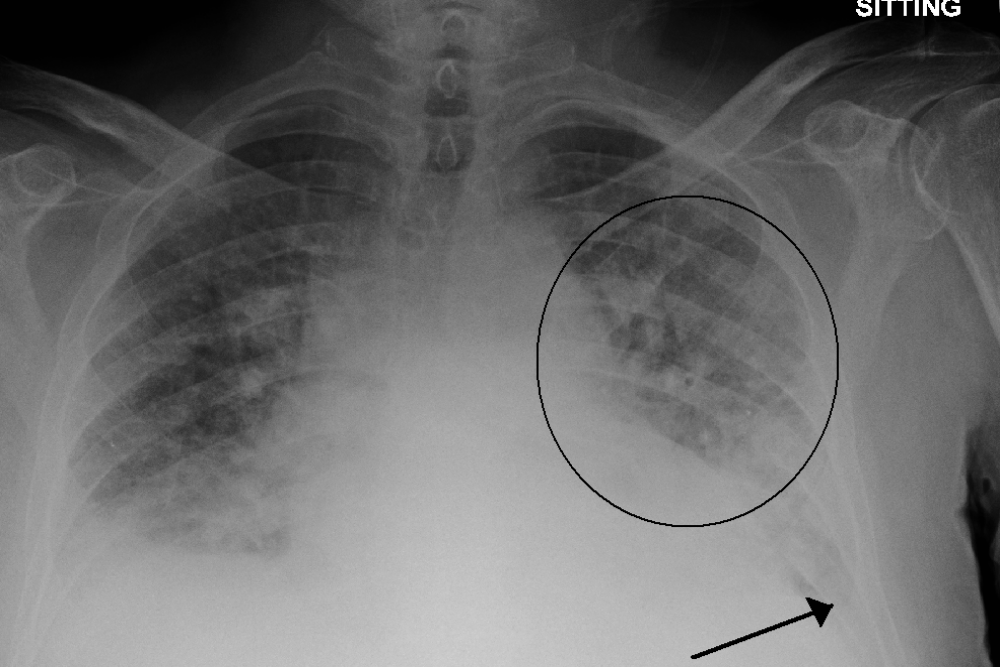

Every year, roughly one out of eight U.S. deaths is caused at least in part by heart failure. One of acute heart failure’s most common warning signs is excess fluid in the lungs, a condition known as “pulmonary edema.”  A patient’s exact level of excess fluid often dictates the doctor’s course of action, but making such determinations is difficult and requires clinicians to rely on subtle features in X-rays that sometimes lead to inconsistent diagnoses and treatment plans. To better handle that kind of nuance, a group led by researchers at…